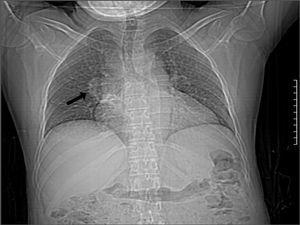

Figura 1. Imagen que muestra engrosamiento del hilio pulmonar derecho.

Mujer de 38 años, con trasplante renal de donante cadáver normofuncionante desde hace 3 años, tratada con prednisona, azatioprina y ciclosporina, que ingresa en nuestro servicio con cuadro de neumonía de lenta resolución y creatinina sérica de 0,9 mg/dl. En la radiografía de tórax se constata una imagen nodular en el hilio pulmonar derecho (figura 1). Se solicita una TC (figura 2) en la que se comprueba una masa sólida en el bronquio segmentario superior derecho asociada con lesiones inflamatorias del parénquima. Se realiza fibrobroncoscopia, observándose una tumoración que hace relieve endobronquial con elementos inflamatorios en su superficie. Se toma biopsia que se envía al Hospital Hermanos Ameijeiras, donde se emite el diagnóstico patológico de un seudotumor inflamatorio por Rhodococcus equi ante el hallazgo de reacción inflamatoria y la comprobación de cocos intramacrófagos, así como cuerpos de Michaelis-Gutman. Esta paciente recibió tratamiento prolongado (60 días) con meropenem y ciprofloxacino, y la imagen tumoral había desaparecido en la tomografía axial computarizada evolutiva realizada tres meses más tarde.